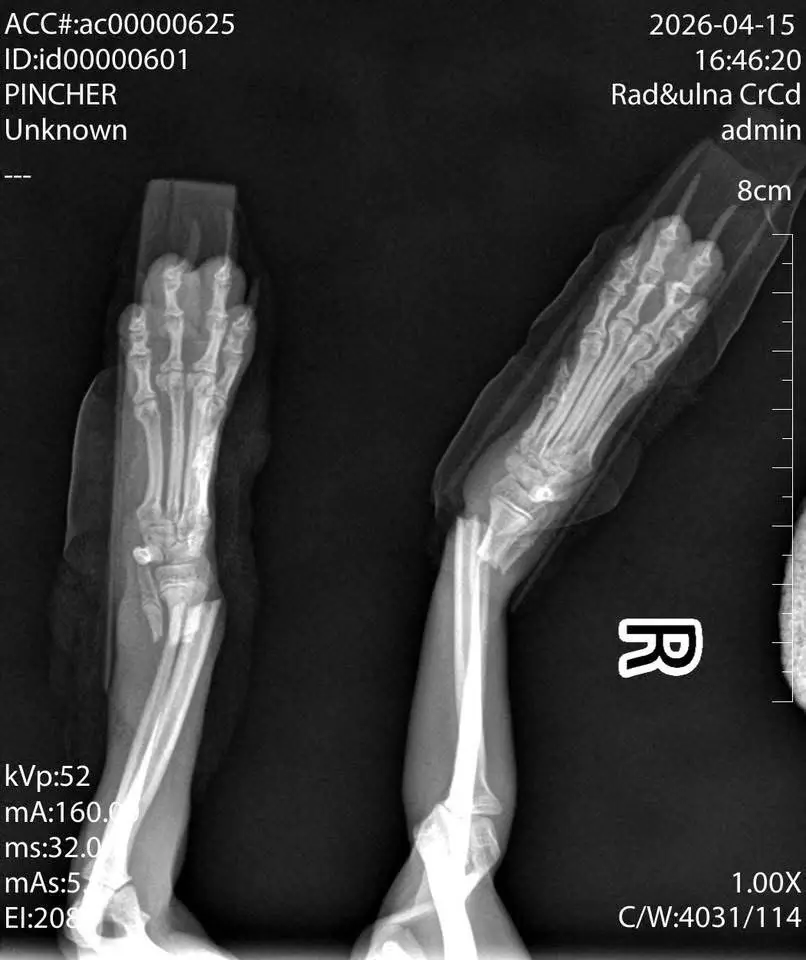

Влизайки в клиниката се разминахме с роми, които изнесоха една шепа кученце навън! Заговорихме се и се оказа,че е паднало от масата и си е счупило двата крака! В клиниката ортопеда беше в отпуска и са им казали,че няма кой да оперира и те са решили да го оставят просто така! Била много скъпа операцията - 1500 евро.

Това за нас беше абсолютно немислимо, след като това малко дребосъче изпитваше ужасни болки.

Защо сумата е 1500 евро?

Микрохирургия: При кученце от 1.5 кг костите са тънки като клечки за зъби. Нужни са специални титаниеви импланти и изключителна прецизност. Денонощни грижи: Айра е твърде малка, за да бъде оставена сама. Тя се нуждае от интензивно наблюдение и венозно обезболяване. Пълно възстановяване: Сумата покрива операцията, престоя и критичните първи дни след интервенцията.